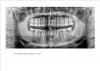

praktik Опубликовано 28 мая, 2011 Поделиться Опубликовано 28 мая, 2011 У вас, в области левого верхнего резца, уже есть убыль кости примерно на 35-40%. После удаления зуба и заживления этого участка возникнет как-бы ямка, которая будет нарушать эстетику при улыбке. С помощью мостовидного протеза, конечно, можно придать этим зубам эстетичный вид, при помощи имитации оголения корня или искусственной десны, но самый быстрый и идеальный, с точки зрения красоты, вариант, это одномоментная установка имплантата сразу после удаления и манипуляции по сохранению ровного контура десны в области основания коронок зубов. Для этого подходят не все системы имплантатов, нужно подбирать определённый. Временный искусственный зуб-не проблема. Ссылка на комментарий

praktik Опубликовано 30 мая, 2011 Поделиться Опубликовано 30 мая, 2011 Наращивать нужно костную ткань под десной, а после этого, возможно делать пластику десны, нужно смотреть воочию. У вас упущено время, много кости возле корня отсутствует, поэтому если хотите красиво, надо набраться терпения и восстанавливать этот зуб, скорее всего, надо в два этапа, а может и в три. Реконструкция по вертикали самая сложная. А имплантат подбирается по ситуации, на эту тему можно рассуждать очень долго... Ссылка на комментарий